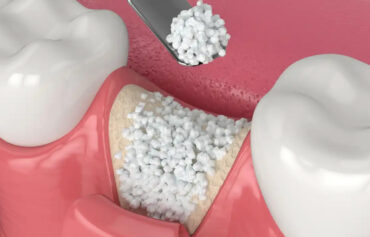

Dr. Patel’s philosophy centersaround providing a patient-first experience, where the highest standards of care are delivered with compassion and precision. She uses advanced tools such as the NSK endomotor, J. Morita apex locator, high-class Vatech X-ray setup, and an in-house dental scanner for accurate diagnosis and treatment. The clinic also specializes in a wide range of dental services, including root canal therapy, wisdom tooth removal, composite fillings, zirconia crowns, E-Max veneers, and much more. For those needing full-mouth rehabilitation, dental implants, or flap surgery, NOVA Dental Hospital offers a comprehensive suite of services with remarkable attention to detail.